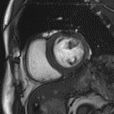

生命感知自由心脏成像平台

MAGNETOM Vida磁共振系统可实现全新的生命感知自由心脏成像:病人进行心脏扫描时,无需配套任何呼吸门控装置,在扫描过程中,磁共振会全程监测病人呼吸以及心电信号,实时控制信号采集;在BioMatrix生命矩阵系统的协助下,Vida可实现业界最快的心脏电影成像,比常规心脏电影成像快10-20倍,可以自由呼吸状态,一个心动周期完成电影采集。

生命感知的自由心脏电影

自由呼吸完成扫描,一个心动周期完成电影采集